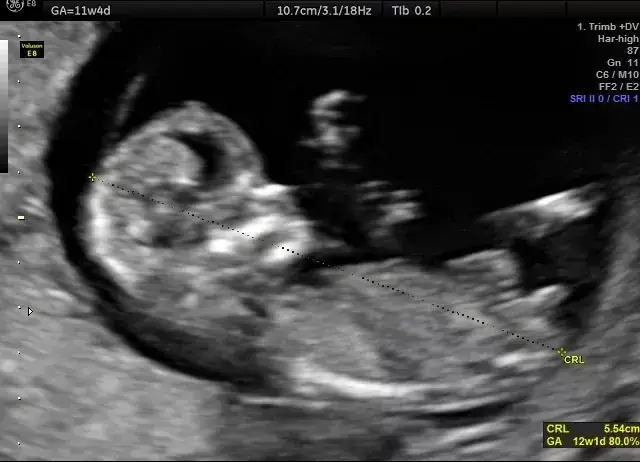

Badanie USG, przeprowadzane od czternastego tygodnia ciąży, umożliwia dokładne pomiary długości płodu od główki do pięt. Standardowe wymiary, takie jak obwód główki i wymiar dwuciemieniowy, również odgrywają istotną rolę w ocenie rozwoju malucha. W niniejszym artykule przedstawimy metody obliczania długości dziecka z USG oraz wyjaśnimy, jak interpretować uzyskane wyniki.

Badanie USG, które można przeprowadzać od czternastego tygodnia ciąży, umożliwia uzyskanie dokładnych pomiarów długości płodu od główki do pięt. Standardowe wymiary, takie jak obwód główki czy wymiar dwuciemieniowy, również odgrywają istotną rolę w ocenie stanu zdrowia malucha. Dzięki tym pomiarom lekarze mogą wczesniej zidentyfikować ewentualne problemy zdrowotne.

Kiedy i jak często wykonuje się USG w ciąży dla pomiarów